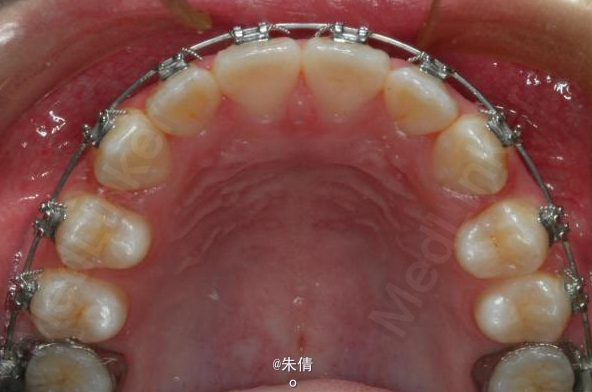

对于面型较好,拥挤度不大的病例,推磨牙向后不失为一种很好的方法,当然现在推磨牙后向的手段和方法很多,但是主要 是适应证的问题。我认为我们在做推磨牙向后,首先是考虑拥挤度,第二个要考虑的是现有的面型,第三点也是很重要的一点,是考虑牙弓后段拥挤度,Tweed-Merryfireld拥挤度的诊断方法将牙弓拥挤度分析分为三段,牙弓前段拥挤度,牙弓中段的拥挤度,以及牙弓后段的拥挤度。不管用什么方法或是手段推磨牙向后,一定不能将牙弓前端矛盾移到牙弓中段或是后段。今天给大家看一直面型,拥挤度不是很大推磨牙向后的病例。希望对大家能有所帮助。